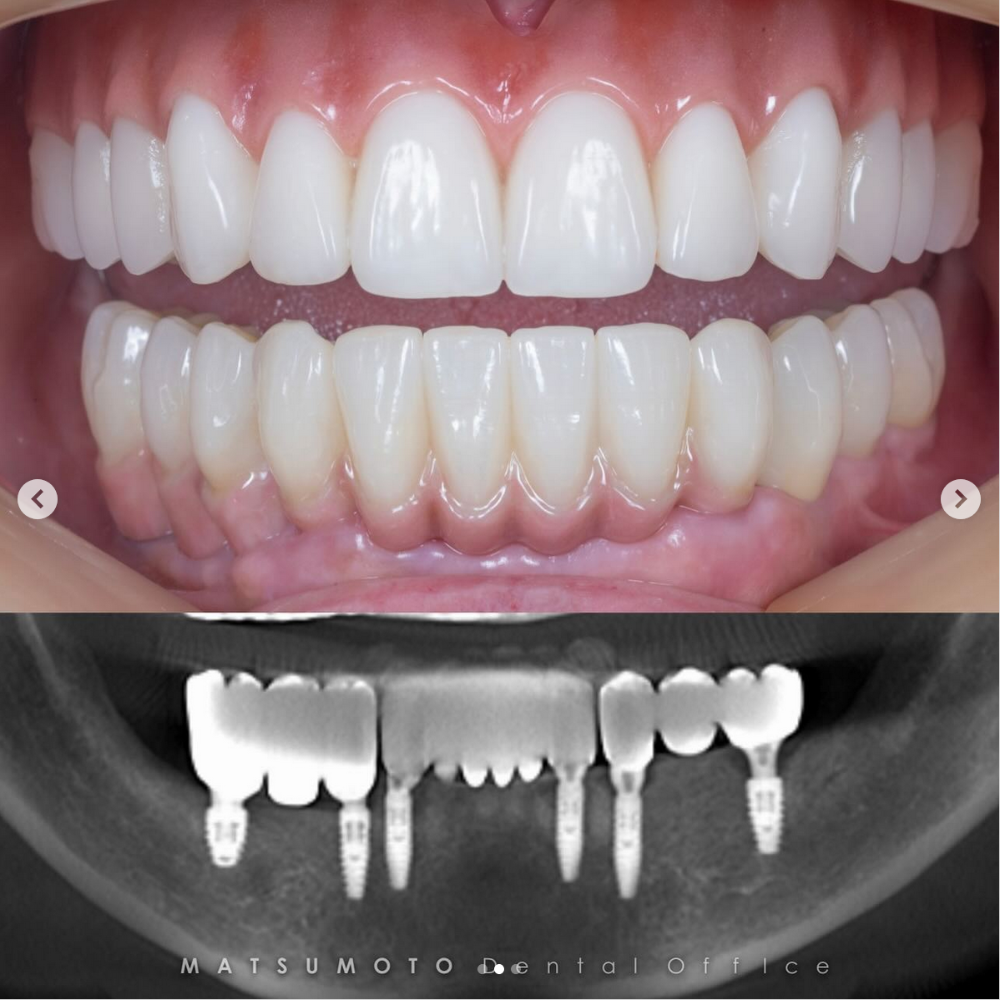

サージカルガイドは、CTで取得した3Dデータに基づいてテンプレートを作成し、シミュレーション通りの精密なインプラント治療を可能にします。骨が薄くなった方でも、正確な治療が可能となり、より痛みや腫れを最小限に抑えることができる先進技術です。

デジタルプランニングとナビゲーションシステムを活用したガイデッドサージェリーにより、正確で安全なインプラント手術を提供しています。患者様には問題点や治療の必要性を視覚的に理解しやすく説明し、安心して治療を受けられるよう配慮しています。

CT画像を基にコンピューターで精密な治療計画を立てる手法により、手術が行われます。この方法では、歯肉に約3ミリメートルの小さな穴を4箇所開けるだけで済みます。また、手術から仮歯装着までの時間が大幅に短縮され、最短で1時間程度で完了します。この技術は術後の出血や腫れ、痛みが格段に少ないことも特長です。

各種検査を行い、CTやレントゲン撮影、口腔内外の写真撮影を実施します。

また、仮歯を作るための型取りも行います。これにより、正確な治療計画を立てることが可能です。

検査結果・デジタルデータをもとに、治療計画を立てます。

抜歯後、顎の骨にインプラントを埋め込みます。手術と同日に、仮歯を装着します。

仮歯は、患者様のお顔に自然に馴染むよう、事前に採取した歯型を元に作成されます。